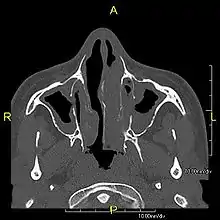

| Complications | Chronic recurrent respiratory infections, including sinusitis, bronchitis, pneumonia, and otitis media.[2] |

Around 80% of people with primary ciliary dyskinesia experience respiratory problems beginning within a day of birth. Many have a collapsed lobe of the lung and blood oxygen low enough to require treatment with supplemental oxygen.[1] Within the first few months of life, most develop a chronic mucus-producing cough and runny nose.[1] The main consequence of impaired ciliary function is reduced or absent mucus clearance from the lungs, and susceptibility to chronic recurrent respiratory infections, including sinusitis, bronchitis, pneumonia, and otitis media. Progressive damage to the respiratory system is common, including progressive bronchiectasis beginning in early childhood, and sinus disease (sometimes becoming severe in adults). However, diagnosis is often missed early in life despite the characteristic signs and symptoms.[2] In males, immotility of sperm can lead to infertility, although conception remains possible through the use of in vitro fertilization, there also are reported cases where sperm were able to move.[8] Trials have also shown that there is a marked reduction in fertility in females with Kartagener's syndrome due to dysfunction of the oviductal cilia.[9]

Many affected individuals experience hearing loss and show symptoms of otitis media which demonstrates variable responsiveness to the insertion of myringotomy tubes or grommets. Some patients have a poor sense of smell, which is believed to accompany high mucus production in the sinuses (although others report normal – or even acute – sensitivity to smell and taste). Clinical progression of the disease is variable, with lung transplantation required in severe cases. Susceptibility to infections can be drastically reduced by an early diagnosis. Treatment with various chest physiotherapy techniques has been observed to reduce the incidence of lung infection and to slow the progression of bronchiectasis dramatically. Aggressive treatment of sinus disease beginning at an early age is believed to slow long-term sinus damage (although this has not yet been adequately documented). Aggressive measures to enhance clearance of mucus, prevent respiratory infections, and treat bacterial superinfections have been observed to slow lung-disease progression. The predicted incidence is 1 in approximately 7500.[10]